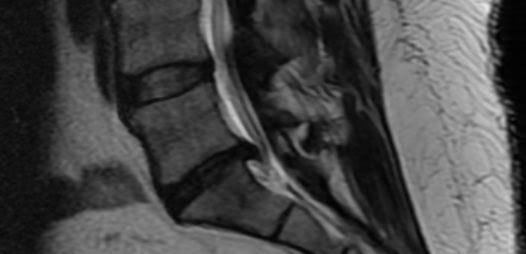

I just had an MRI done and they gave me a disk to take with me for a Doc that will be calling me.

Can anyone tell me how bad is it? Just a heads up on what can be expected.

I won't hold you to your diagnosis.